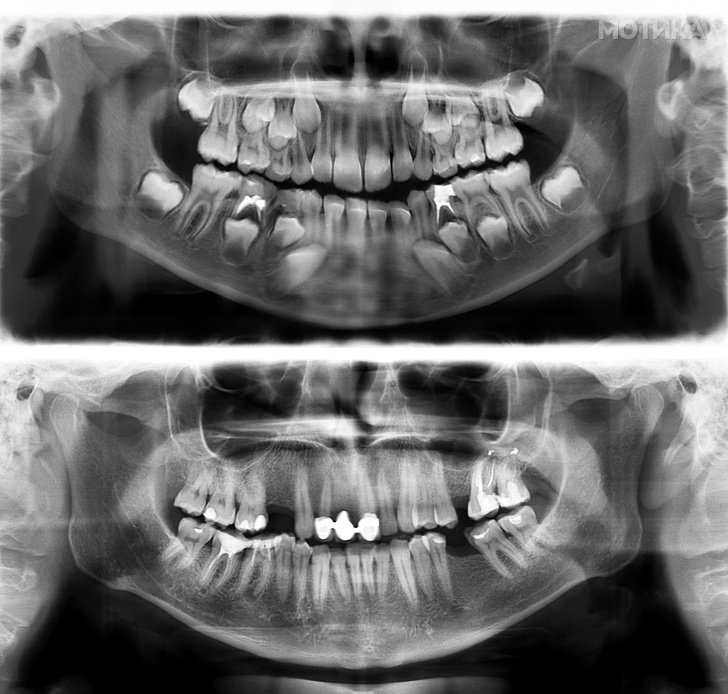

17. Вака изгледаат човечките заби на 7 и на 30 години